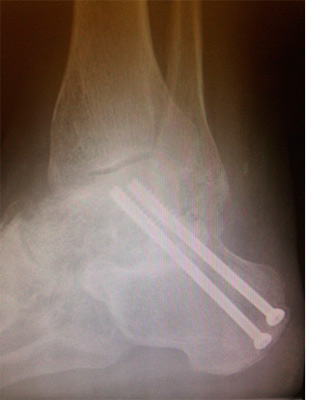

Артродез кисти

Артродез кисти 114 фотографий